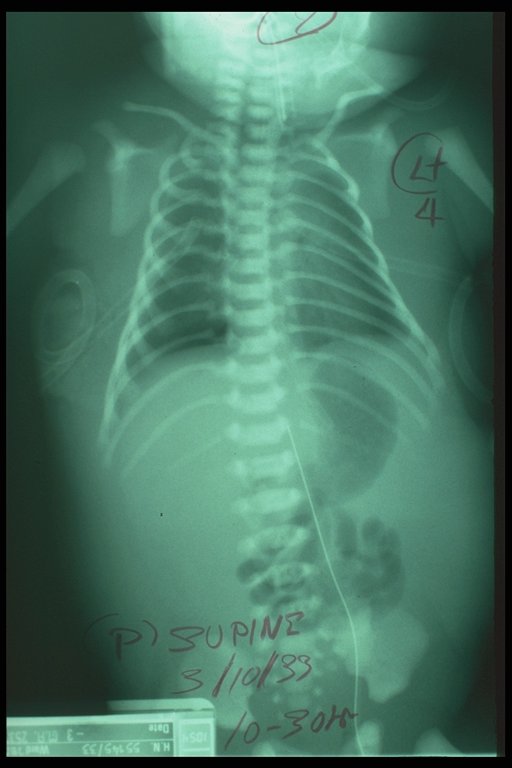

Ten days after intercostal drainage of bilateral chylothorax. The baby could breathe without any assistant. Both lungs expanded well and less edema was noted.